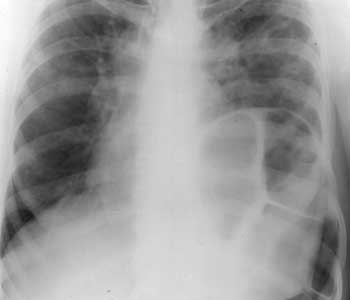

Диагностика образований, расположенных в проекции кардио-диафрагмальных углов.

Рис. 4. Диафрагмальная грыжа слева. Содержит петлю толстой кишки.